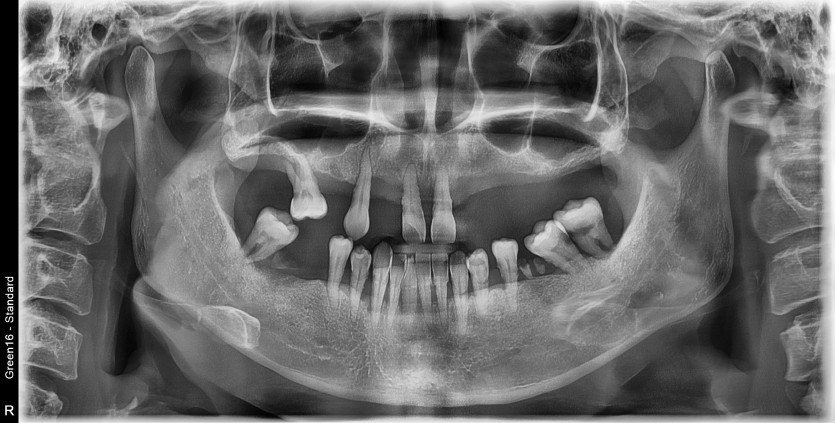

만 45세 전체 임플란트 증례

전체 임플란트 증례입니다.

18개의 임플란트로 완성하였습니다.